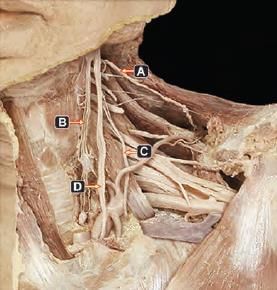

Which of the following arrow marked nerves, if injured present with paradoxical breathing? (INI-CET Nov 2020)

NOT an anatomical landmark of facial nerve identification in parotid surgery: (NEET-PG 2020p)

Post parotidectomy, patient feels numb while shaving. Which nerve was involved? (AIIMS May 2019)